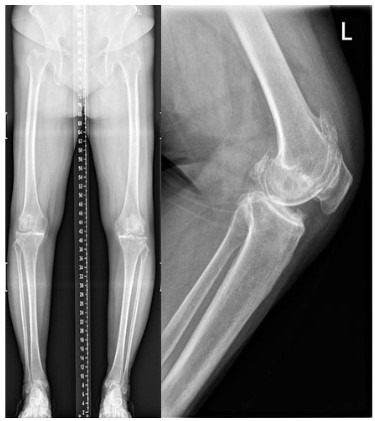

A female, aged 55, with 153 cm in height, 85 kg in weight and 36.3 in BMI. She was admitted to hospital on July 24, 2021 due to severe osteoarthritis of the right knee. Physical examination manifested severe varus deformity of affected limb with limited flexion and extension activities, with ROM: 80°-10°-0° (Figure 1). The patient received TKR on July 27, 2021. She was permitted walking one day post-operatively, and was discharged one week later (Figure 2).

Figure 2: Case 1 after knee replacement

Case 2 was also a female with 58 in age, 160 cm in height, 65 kg in weight and 25.4 in BMI. She was admitted to hospital on December 08, 2020 due to severe osteoarthritis of the left knee. Physical examination manifested severe deformity of the affect limb with limited flexion and extension activities, with ROM: 100°-10°-0° (Figure 5).

TKR was implemented for her left knee under general anesthesia on December 08, 2020. And 1 day later after surgery, she began to walk with crutches (Figure 6). The patient was discharged 1 week post-operatively with satisfactory recovery.

Figure 6: Case 2 after knee replacement

As for the reasons, we deduced that post-operative changes in biomechanical axis of knee joint, increasing activity levels, osteoporosis and BMI mass index played great role in leading to stress fracture of femoral neck. Furthermore, the bilateral varus deformity of the knee joint was severe in these two patients, lower limb load axis after TKR is significant changed (Figures 1,2,5,6), resulting in concentrated creation on the femoral neck cortex. When full weight bearing, activity levels increased and excessive loading of the hip may cause the tendency of hip varus, bring about the possibility of fracture. Those two patients (Tables 1,2), Osteoporosis index 25 hydroxyvitamin D was lower than normal, they are osteoporosis, Bone density and mass decrease, and bone microstructure is destroyed, resulting in increased bone fragility, which can lead to fractures. The BMI of case 1 is 36.3, severe obesity, excessive loading of the right hip, so we assume that changes in biomechanical axis of knee joint after TKR, activity levels increased, osteoporosis and BMI mass index can lead this infrequent complication.